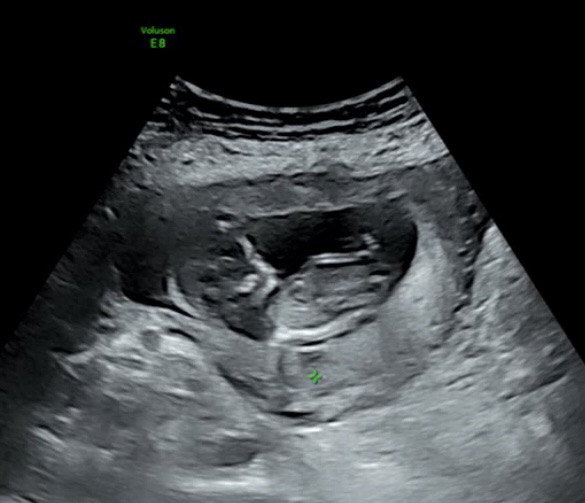

각도법 고수님들 성별이 어떨지 보일까요? 아직 병원에선 알려주시지 않으셔서 너무 궁금해서 여쭤봐요ㅠㅠㅠㅠ 예전초음파 사진 첨부해요 ! 지금은 14주 입니다ㅠㅠ

아기 척추뼈랑 돌기가 잘 안 보이긴 해요. 유추하면 딸 각도 같습니다.